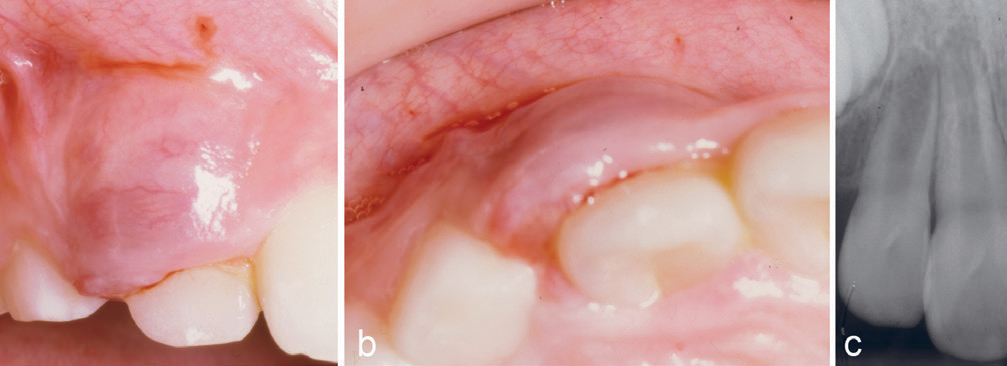

Kasus 3

En ni år gammel gutt ble henvist fra sin tannlege for fjerning av hemangiom. Ved klinisk undersøkelse var der en hevelse buccalt for tann 12. Den var blå-rød av farge og var fastere enn et hemangiom vanligvis er. Den dekket halve kronen buccalt ved 12 (figur 3a, b), og det var ikke noen patologiske forandringer å se på røntgen (figur 3c). Lesjonen ble fjernet og benoverflaten dekket med salveveke. Den kliniske diagnosen PKCG ble bekreftet histologisk. Det ble sekundær epitelialisering, og kontroll seks måneder postoperativt viste intet residiv.

Figur 3. Kasus 3. PKCG buccalt for 12 hos en ni år gammel gutt (a, b). Røntgen (c) viste ingen patologiske forandringer.